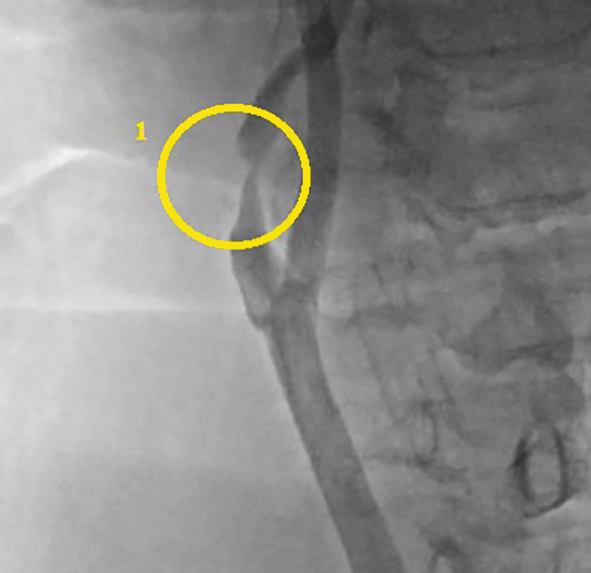

Пациент А., 68 лет, мужчина. В 2015 г. поступил в неврологическое отделение ГБУЗ «Городская Александровская больница» с клиникой транзиторной ишемической атаки в вертебробазилярном бассейне. При обследовании по данным мультиспиральной компьютерной томографии с ангиографией у больного визуализирован 80% стеноз левой ВСА (рис. 1).

Рис. 1. Мультиспиральная компьютерная томография с ангиографией брахиоцефальных артерий: 1 — 80% стеноз левой ВСА. / Fig. 1. Multispiral computed tomography and brachiocephalic angiography: 1 — 80% left ICA stenosis.